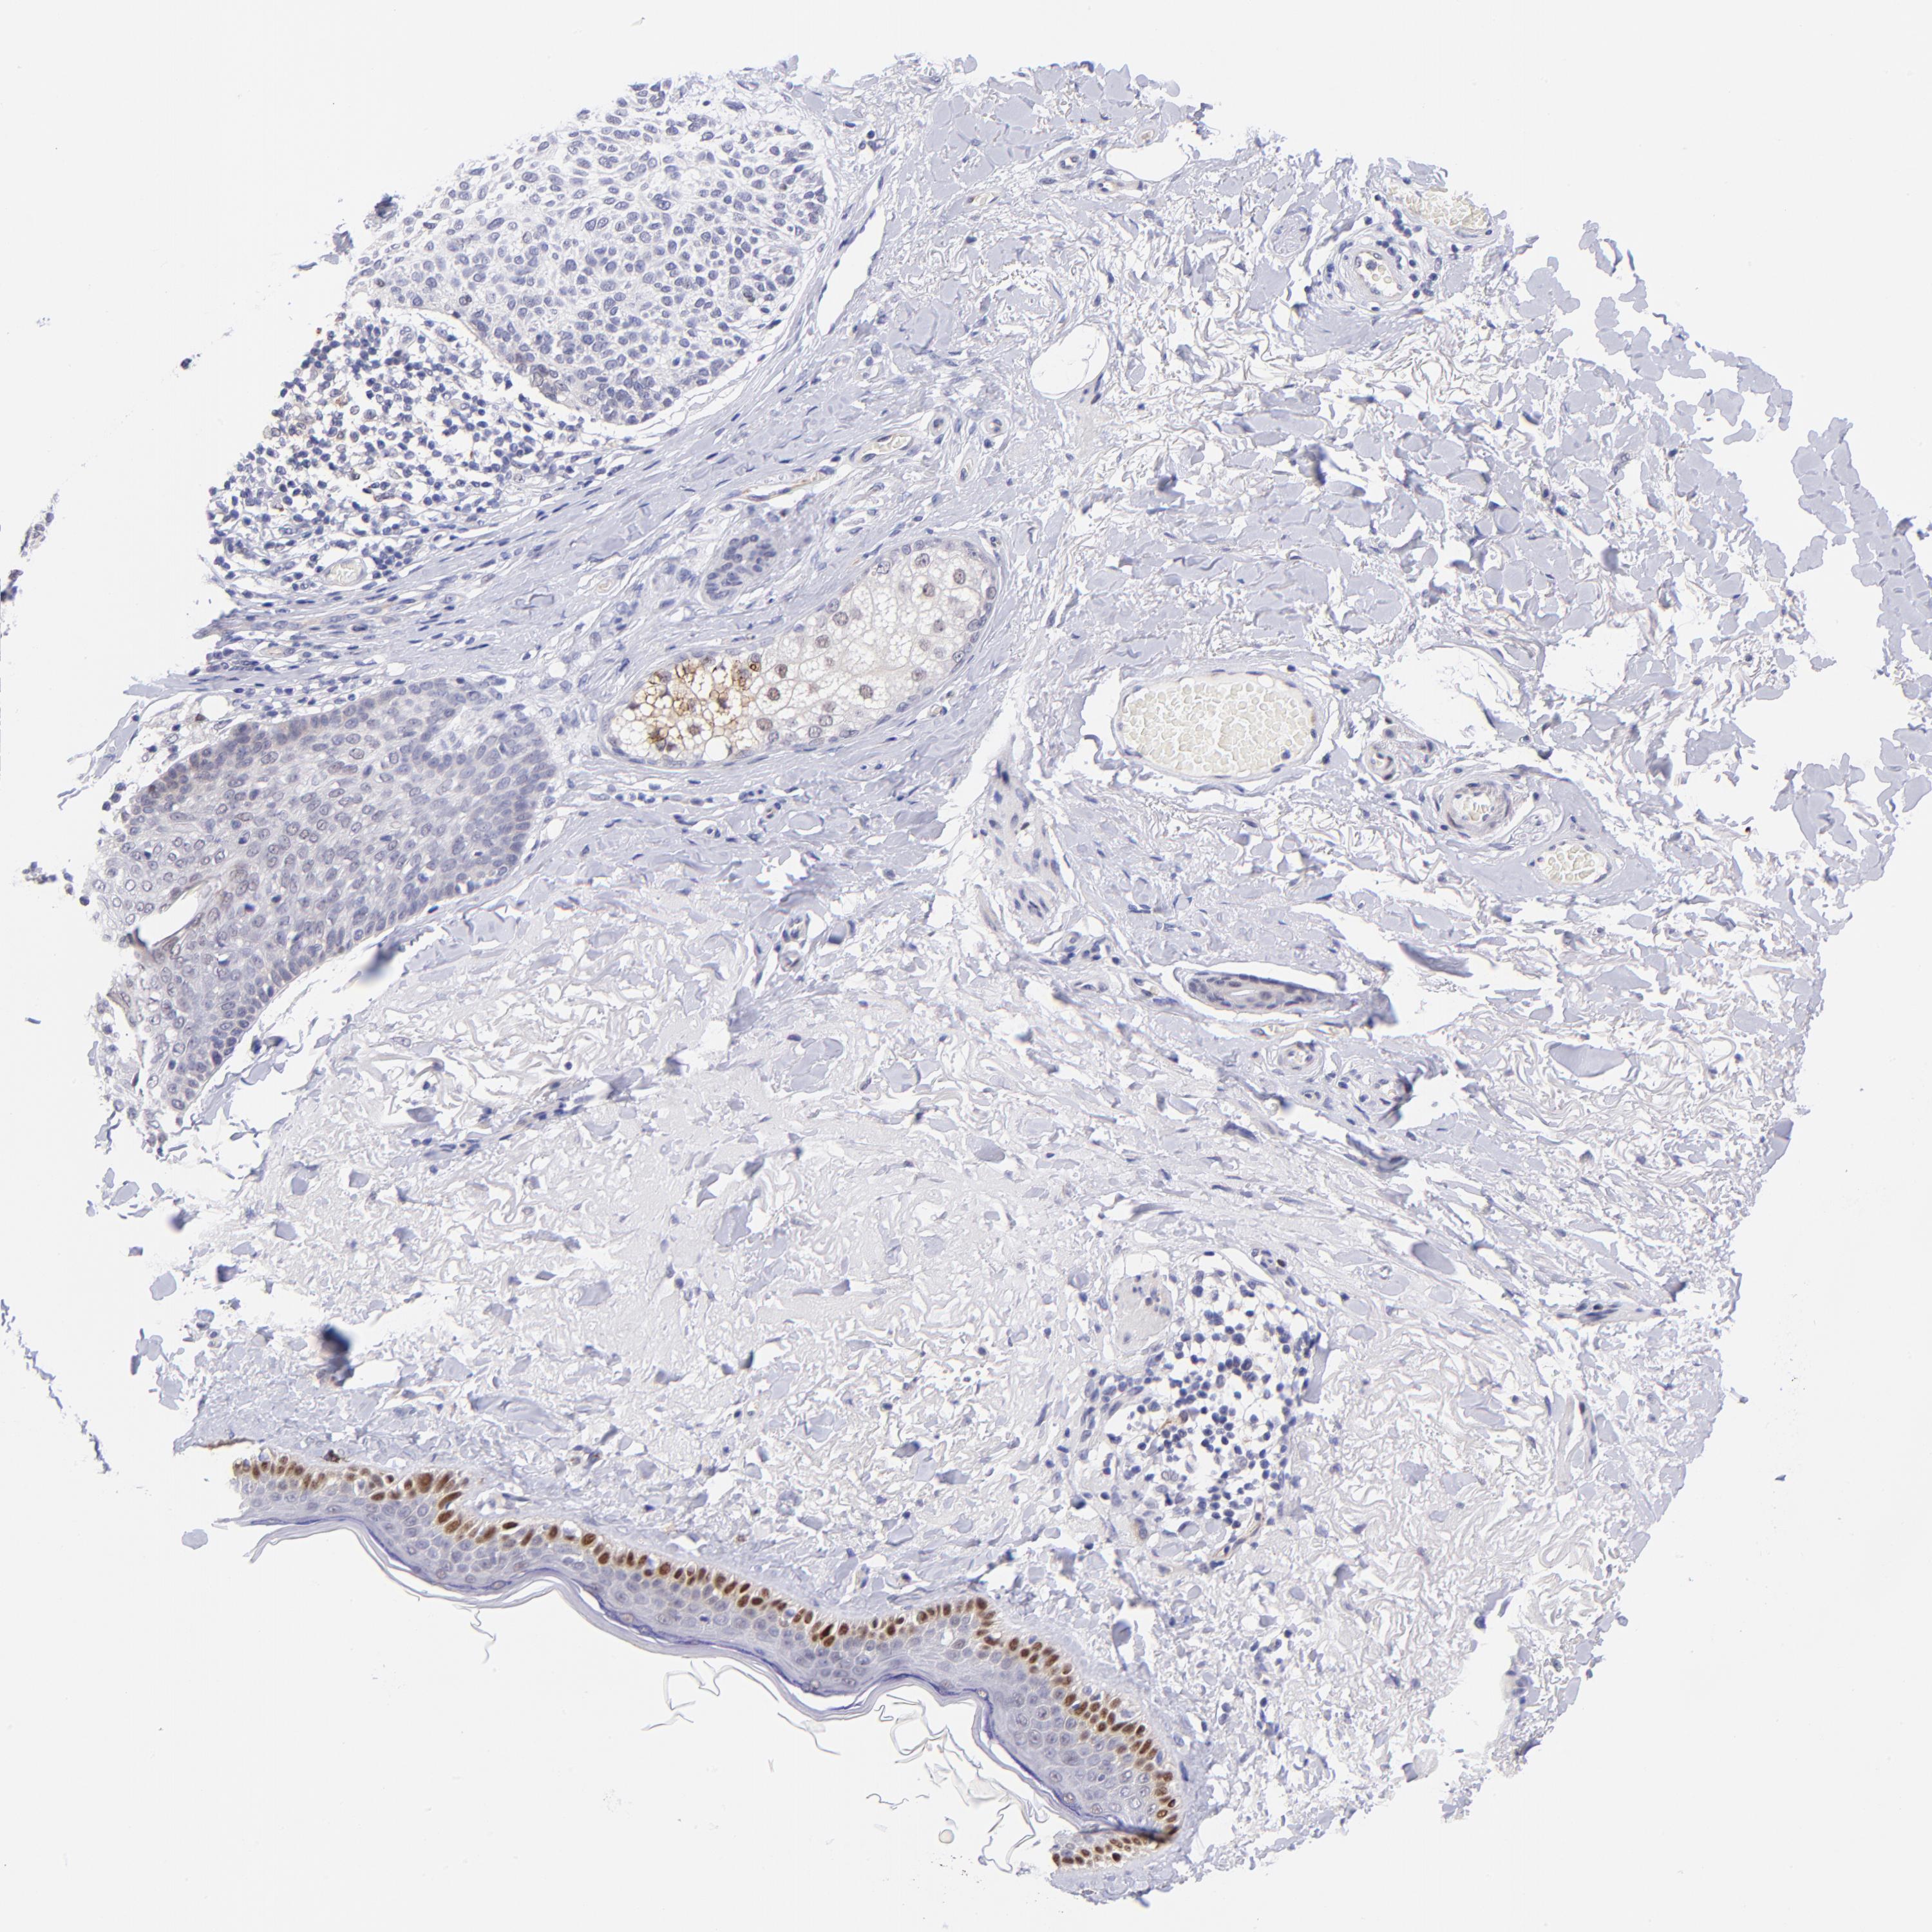

SKIN CANCER - Protein expressioni

A mouse-over function shows sample information and annotation data. Click on an image to view it in a full screen mode. Samples can be filtered based on level of antibody staining by selecting one or several of the following categories: high, medium, low and not detected. The assay and annotation is described here.

Antibody stainingi

Antibody staining in the annotated cell types in the current human tissue is reported as not detected, low, medium, or high, based on conventional immunohistochemistry profiling in selected tissues. This score is based on the combination of the staining intensity and fraction of stained cells.

Each image is clickable and will lead to virtual microscopy that enables deeper exploration of all samples and also displays staining intensity scores, fraction scores and subcellular localization as well as patient and tissue information for each sample.

Antibody HPA001923

Antibody HPA003908

Squamous cell carcinoma, NOS

Basal cell carcinoma